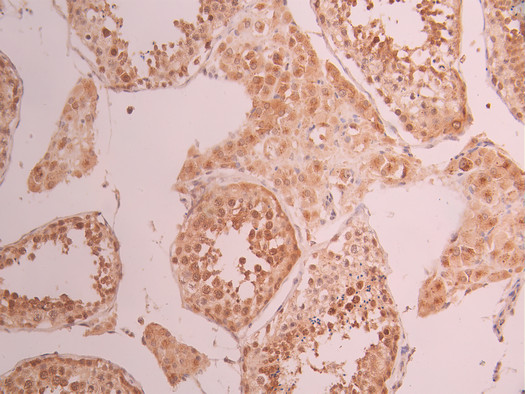

IHC image of CSB-RA172307A0HU diluted at 1:100 and staining in paraffin-embedded human testis tissue performed on a Leica BondTM system. After dewaxing and hydration, antigen retrieval was mediated by high pressure in a citrate buffer (pH 6.0). Section was blocked with 10% normal goat serum 30min at RT. Then primary antibody (1% BSA) was incubated at 4°C overnight. The primary is detected by a Goat anti-rabbit polymer IgG labeled by HRP and visualized using 0.05% DAB.